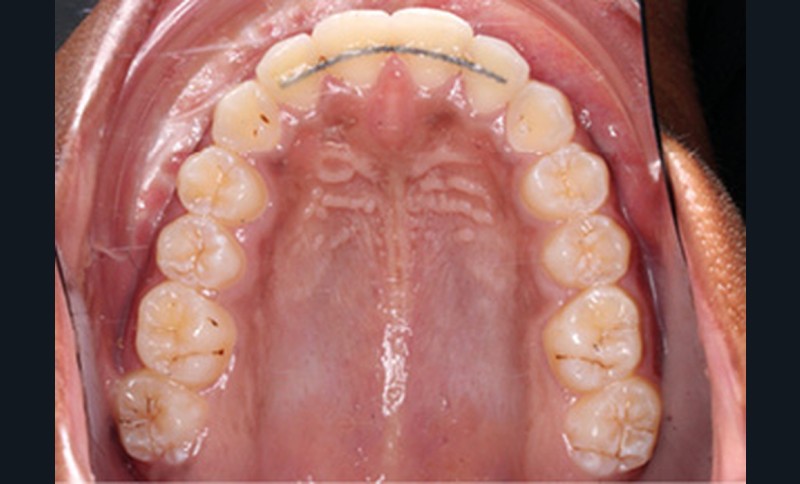

Examen clinique (fig. 1a-h)

L’examen clinique endo-buccal révèle une denture adulte jeune avec un inversé d’articulé antérieur de 13 à 23, des tatouages gingivaux ethniques et des taches de décalcifications, un parodonte sain mais un brossage insuffisant.

L’arcade maxillaire est en V et la voûte palatine profonde. L’arcade mandibulaire a une forme en U (non-concordance des formes d’arcade) et présente des malpositions des dents cuspidées. La médiane mandibulaire est décalée à gauche de 2 mm ; le recouvrement antérieur est de 2 mm ; les molaires sont en classe III avec un surplomb inversé.

Un protocole ortho-chirurgical en chirurgie première a été retenu. Les étapes de traitement ont été les suivantes : motivation à l’hygiène bucco-dentaire et rééducation des fonctions, puis pose de l’appareil multi-attache edgewise conventionnel avec des arcs aciers .016x.022 passifs adaptés aux deux formes d’arcades, et enfin avancée de 6 mm et génioplastie d’avancée sur ces mêmes arcs.

Les finitions orthodontiques d’intercuspidation et de parallèlisation des axes ont été réalisées sur arcs TMA .019x.025 et élastiques interarcades de classe III 6 mm 4 oz puis triangle d’intercuspidation 4 mm 6 oz. Enfin, le dispositif de contention a consisté en fils collés 2-2 maxillaire et 3-3 mandibulaire et gouttière thermoformée maxillaire.